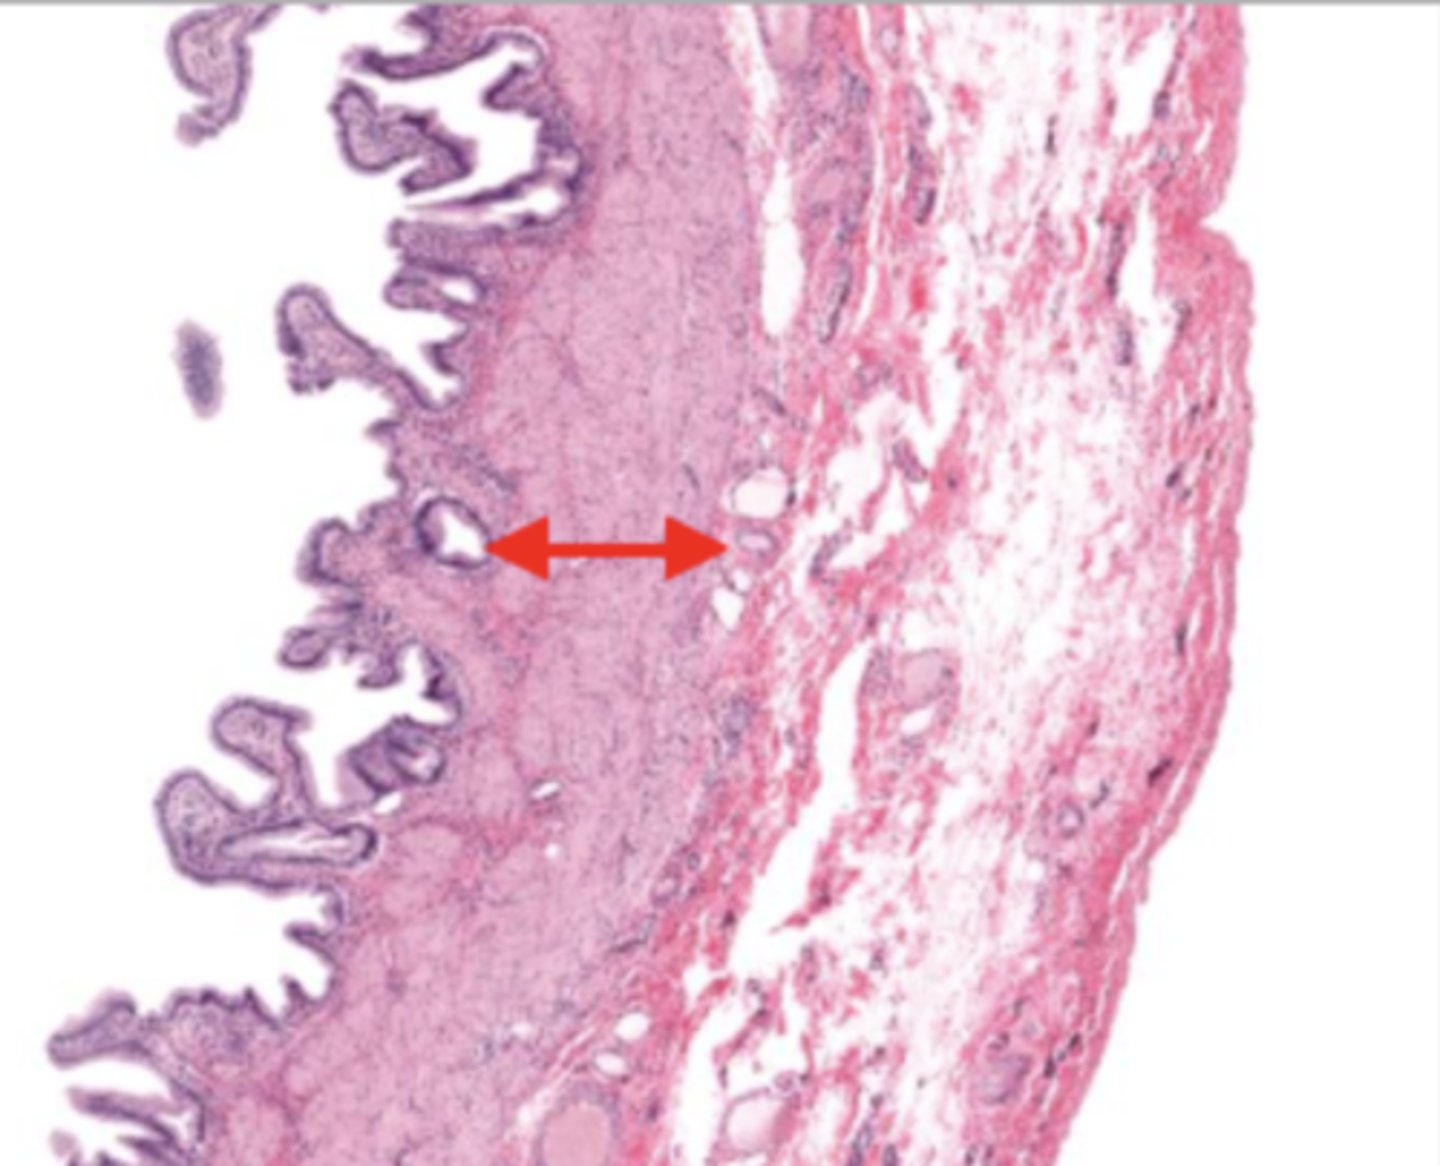

jejunum (histology)

villi (jejunum)

intestinal crypts (jejunum)

lumen (jejunum)

mucosa (jejunum)

mucosal epithelium (jejunum)

lamina propria (jejunum)

muscularis mucosa (jejunum)

submucosa (jejunum)

contains glands and blood supply

muscularis externa (jejunum)

serosa/adventitia (jejunum)